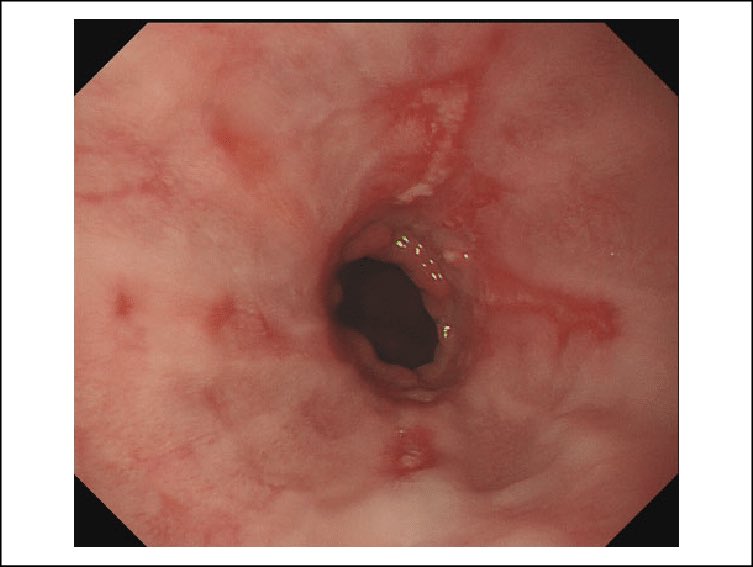

١. منظار المعدة

٣. منظارالمريء مع بالون لتوسيع السوار